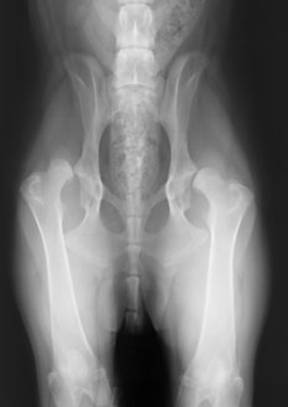

Hochgradige HD